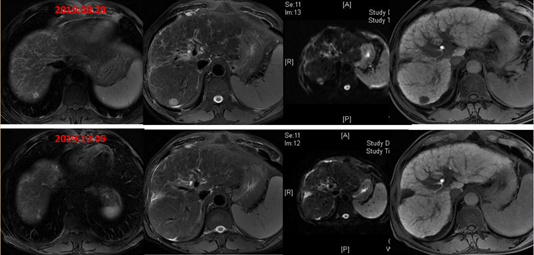

2019年12月5日(术后21个月,更改方案后2个月)进行影像学复查,疗效评价为达到PR,直至2020年6月11日(术后27个月)复查仍为PR状态,肿瘤标志物降至正常。

图:影像学检查(第一行:2019-8-29,第二、三行:2019-12-5,第四行:2020-6-11)